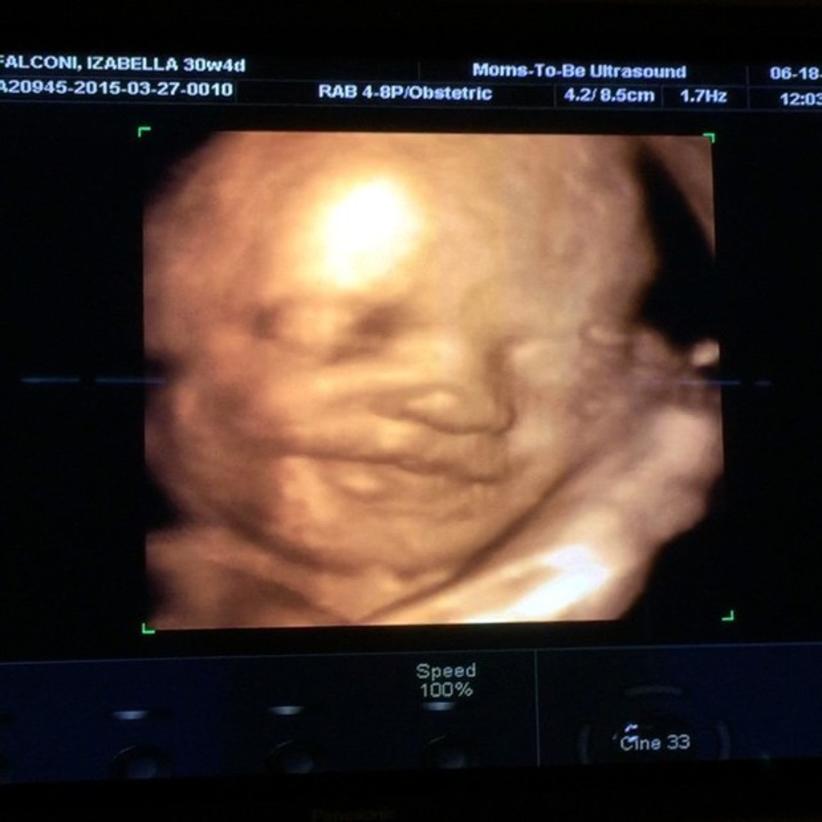

Bella Falconi está feliz com a chegada da primeira filha, Victoria, e mostrou o rostinho da menina para os fãs.

Aos 7 meses de gestação, a musa fitness compartilhou uma imagem do ultrasson 4D no Instagram. “Apresento a vocês o bebê sorriso. (Risos) @mybabyvicky sempre sorridente e de bem com a vida. Que benção! Obrigada mais uma vez! Vocês são incríveis! Melhor ultrassom 4D de Orlando! Se vierem fazer o enxoval nos EUA, não deixem de passar aqui mamães! O Fábio é um amor e fala português! Super recomendo!”, escreveu.